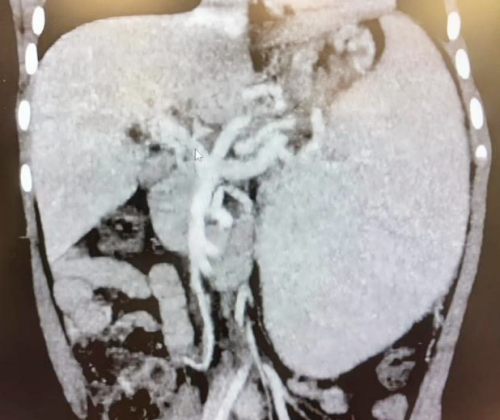

历时10小时17分钟的连续奋战,手术成功最终取得圆满成功。术中超声显示,桥血管血流通畅,出血仅150ml。术后CTA检查证实,重建血管通畅,门静脉高压根本缓解,患儿消化道再出血的风险彻底解除。

术后血管重建影像:肝门搭桥血管血流通畅、脾脏较术前缩小